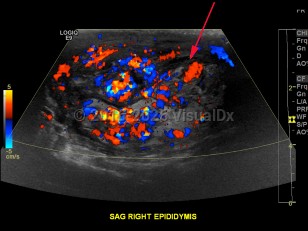

Epididymo-orchitis

Symptoms of epididymo-orchitis usually develop over 1-2 days, although some patients will complain of a more gradual onset of symptoms. The primary complaint is swelling of the scrotum associated with pain. Urethral discharge is common. Fever may or may not be present. On palpation, swelling in the posterior scrotum localized over the involved epididymis can be appreciated. There may be a hydrocele. There may be erythema overlying the area of swelling. Pain should improve within 72 hours after treatment, although inflammation may persist for a few weeks.